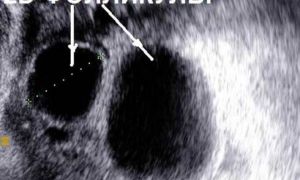

- Трансвагинальное узи- очень ценный диагностический инструмент,который позволяет увидеть изменения при остром аднексите и тубоовариальном образовании. При помощи узи можно дифференцировать боль при эндометриозе, эндометрите, остром аппендиците, разрыве кисты яичника, почечной колике и при многих других заболеваниях, сопровождающихся болью внизу живота